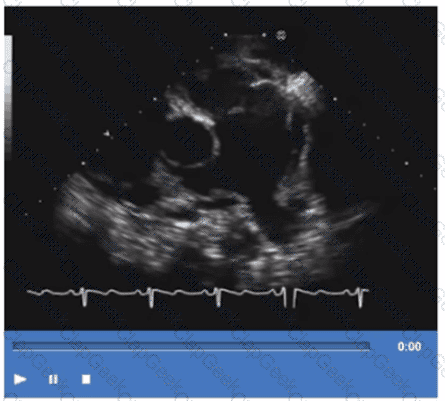

Identify the right pulmonary artery.

Using your mouse, place the cursor on the appropriate region of the image and then left click the mouse button to indicate your selection.